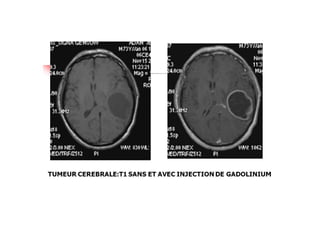

MENINGIOME:

TDM et IRM avant et après injection de produit de

contraste

Avant injection de produit de contraste :

– TDM: Formation extra axiale spontanément

hyperdense homogène.

– Hyperostose ou ostéo condensation

adjacente(fenêtre osseuse)

IRM: signal intermédiaire en T1 , hypersignalT2 et

FLAIR

– Œdème péri tumoral: hypo dense en TDM .

– hyposignalT1 hypersignalT2 en IRM

– Effet de masse: sur le système ventriculaire

homolatéral à la lésion qui peut être collabé et les

structures médianes qui peuvent être refoulées (

épiphyse , V3 et faux du cerveau)

Après injection de produit de contraste :

Prise de contraste( rehaussement) intense, homogène

• Tumeurs vascularisées: :  augmentation des densités

tumorales

Oedème péri tumoral

MENINGIOME: TDM et IRMavant et après injection de produit de contraste Avant injection de produit de contraste : – TDM: Formation extra axiale spontanément hyperdense homogène. – Hyperostose ou ostéo condensation adjacente(fenêtre osseuse) IRM: signal intermédiaire en T1 , hypersignalT2 et FLAIR – Œdème péri tumoral: hypo dense en TDM . – hyposignalT1 hypersignalT2 en IRM – Effet de masse: sur le système ventriculaire homolatéral à la lésion qui peut être collabé et les structures médianes qui peuvent être refoulées ( épiphyse , V3 et faux du cerveau)

• 26.

Après injection deproduit de contraste : Prise de contraste( rehaussement) intense, homogène • Tumeurs vascularisées: :  augmentation des densités tumorales Oedème péri tumoral • GLIOBLASTOME: Tumeur gliale de haut grade • TDM: Masse hypodense intra axiale hétérogène par la présence de calcifications ou d’hémorragie intra tumorale • Rehaussement hétérogène • Œdème péri lésionnel important avec Effet de masse • IRM: examen clé+++. • Etude multiplanaire en séquences pondérées T1,T2,T2flair,T2*,T1gado(séquences morphologiques).